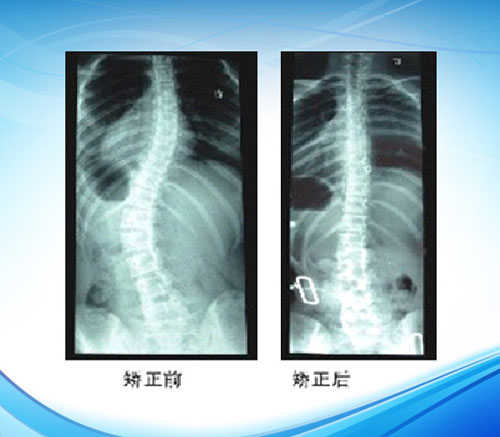

矫正结果的检验

检查矫形器的矫正结果不仅通过比较装配前后(装配后是指适应性练习完成两个星期之后) X线片侧弯角度进行检查,还要检查以下各点细节: